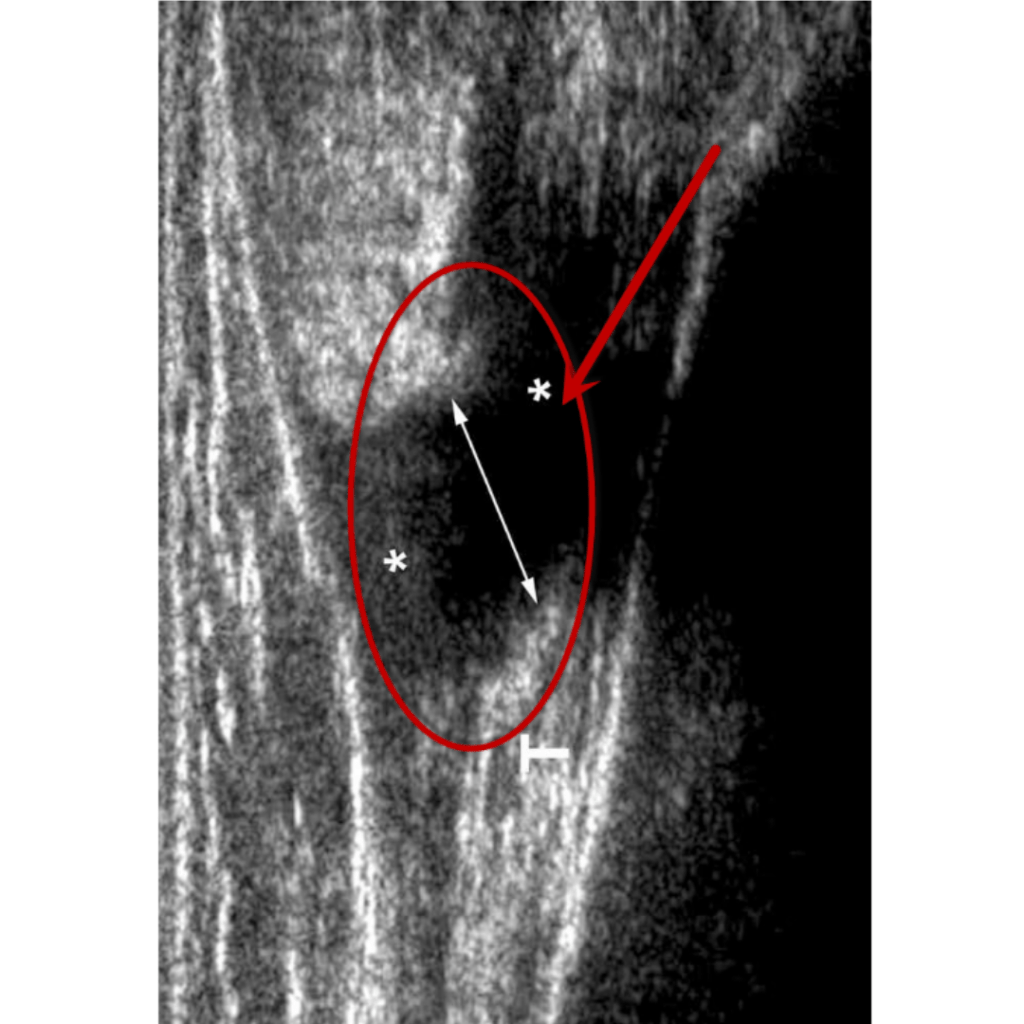

El diagnóstico de esta afectación dependerá mucho de su localización, en caso de sospecha de compromiso en un músculo superficial se puede hacer uso de ecografía (ultrasonido), en tejidos más profundos es más eficiente una resonancia magnética.

Ultrasonido

Ruptura total Grado III